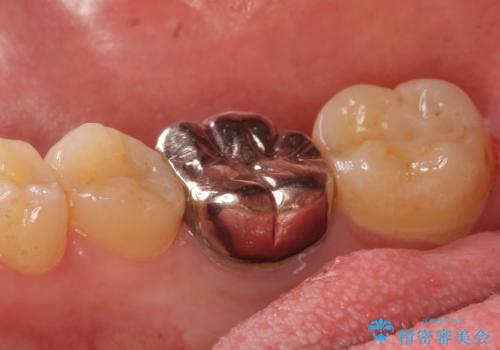

- 右下の奥歯の鈍い痛みがずっと続いているので診て欲しいといらっしゃった方の症例です。

検査の結果右下6に根尖病変を認めたため、再根管治療を行いました。

その後症状の消失を確認し、オールセラミッククラウンによる補綴を行いました。